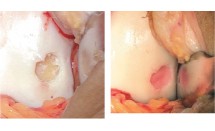

Le laser, une thérapie qui ouvre de nouveaux champs d'application

La thérapie laser, qui existe depuis plus de 30 ans dans les cabinets, a su évoluer et surtout devenir un traitement qui a toute sa place dans l'arsenal thérapeutique du kinésithérapeute. Elle n'est pas qu'un...